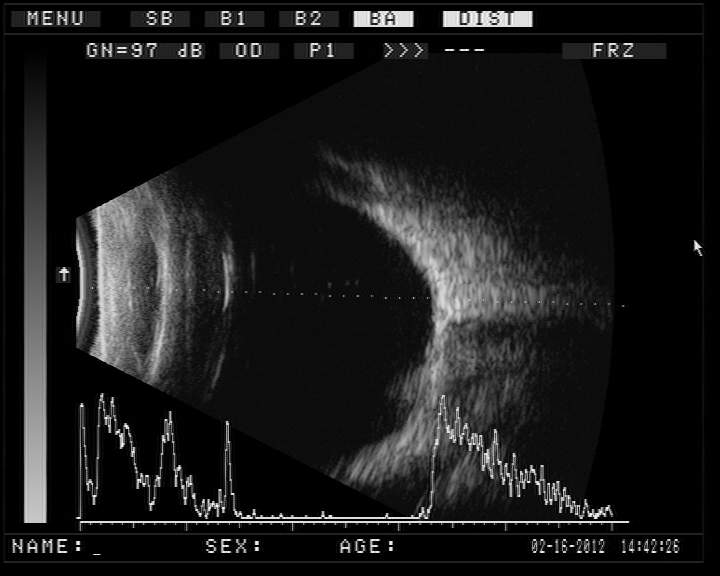

B超提示:玻璃體混濁(雙眼)?高度近視、后鞏膜葡萄腫(右眼)?視網膜脫離(左眼)。??

B超提示高度近視,后鞏膜葡萄腫

B超顯示全網脫